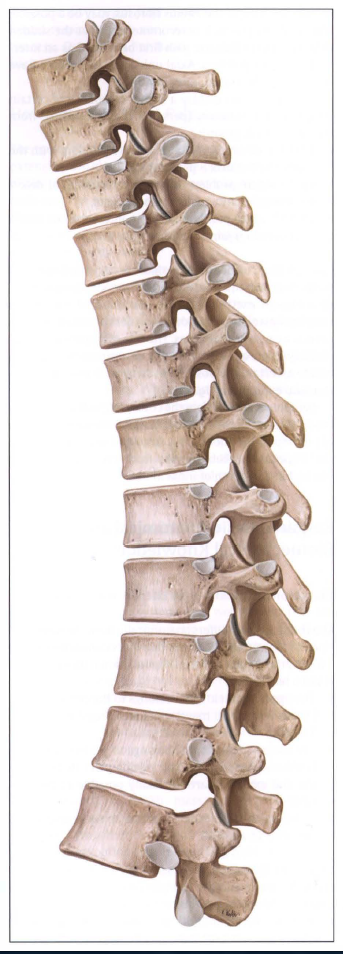

On further inspection, these sections can also be differentiated from one another morphologically (Fig. 1 1 .4). The shape of the two upper thoracic vertebrae is more similar to a cervical vertebra while the lower thoracic vertebrae gradually take on the shape of a lumbar vertebra. Only the spinous processes in the middle section of the thoracic spine slant down typically at a steep angle.

- 흉추 5-10번 시진은 구조로 감별할 수 있음.

- 상부 흉추의 형태는 경추와 유사하고, 하부 흉추의 형태는 요추와 유사함.

- 오직 중부 흉추가 기울어진 각도(아래로)로 내려가 있음.